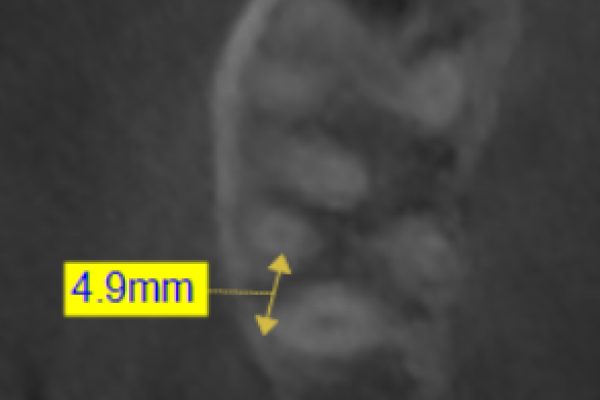

Implantes de 4,5mm de longitud utilizados en atrofia ósea en altura (hueso residual ≤ 4,5m). Estudio retrospectivo